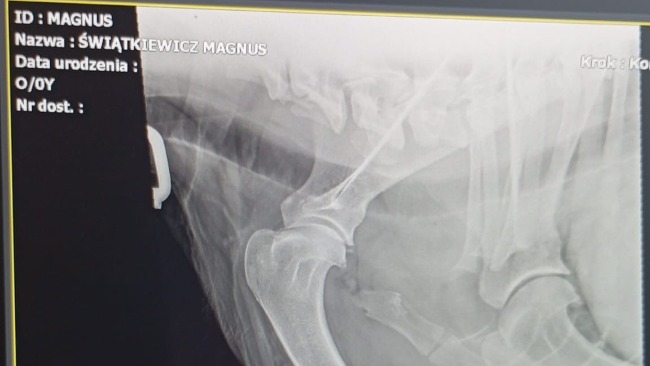

Ze stawów idealnych, nagle padła diagnoza - dysplazja stawu łokciowego HD-3, co za tym idzie zwyrodnienia i degeneracja stawu.

Pod koniec października Magnus miał robione TK (tomografię komputerową) - głównie kręgosłupa, ze względu na spondylozę na odcinku L6-L7, ale też ponownie, kontrolnie prześwietliliśmy stawy (przód i tył).

•Wstępna diagnostyka + RTG (na cito, jak nagle zaczął kuleć) - 400 zł

•Konsultacja ortopedyczna w ABvet u dr. Nováka - 1200 zł

•Artroskopia łokcia - 4 000 zł

•Konsultacja ortopedyczna kontrolna, badania, TK + pierwsze osocze podane w Krakowie - 3700 zł